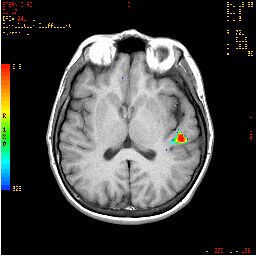

| Activación |

Este paradigma produce como respuesta la activación de la cara superior de las áreas 37 de Broca y Brodmann. Aparece algo de activación en las áreas parietales parasagitales. El color en la fosa pterional izquierda se debe a la entrada de flujo vascular. |